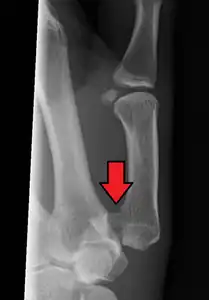

A Bennett fracture is a type of broken finger involving the base of the thumb, which extends into the knuckle joint.[4][1] Symptoms generally include thumb swelling and pain.[1] Associated injuries may include ulnar collateral ligament injury of the thumb or trapezium fracture.[1]

The cause is generally a force along the long axis of the thumb.[1] Diagnosis is supported by X-rays.[1] There is nearly always some degree of disruption of the carpometacarpal joint.[2]

In the case of the Bennett fracture, the proximal metacarpal fragment remains attached to the anterior oblique ligament, which in turn is attached to the tubercle of the trapezium bone of the CMC joint. This ligamentous attachment ensures that the proximal fragment remains in its correct anatomical position.

The distal fragment of the first metacarpal bone possesses the majority of the articular surface of the first CMC joint. Unlike the proximal fracture fragment, strong ligaments and muscle tendons of the hand tend to pull this fragment out of its correct anatomical position.